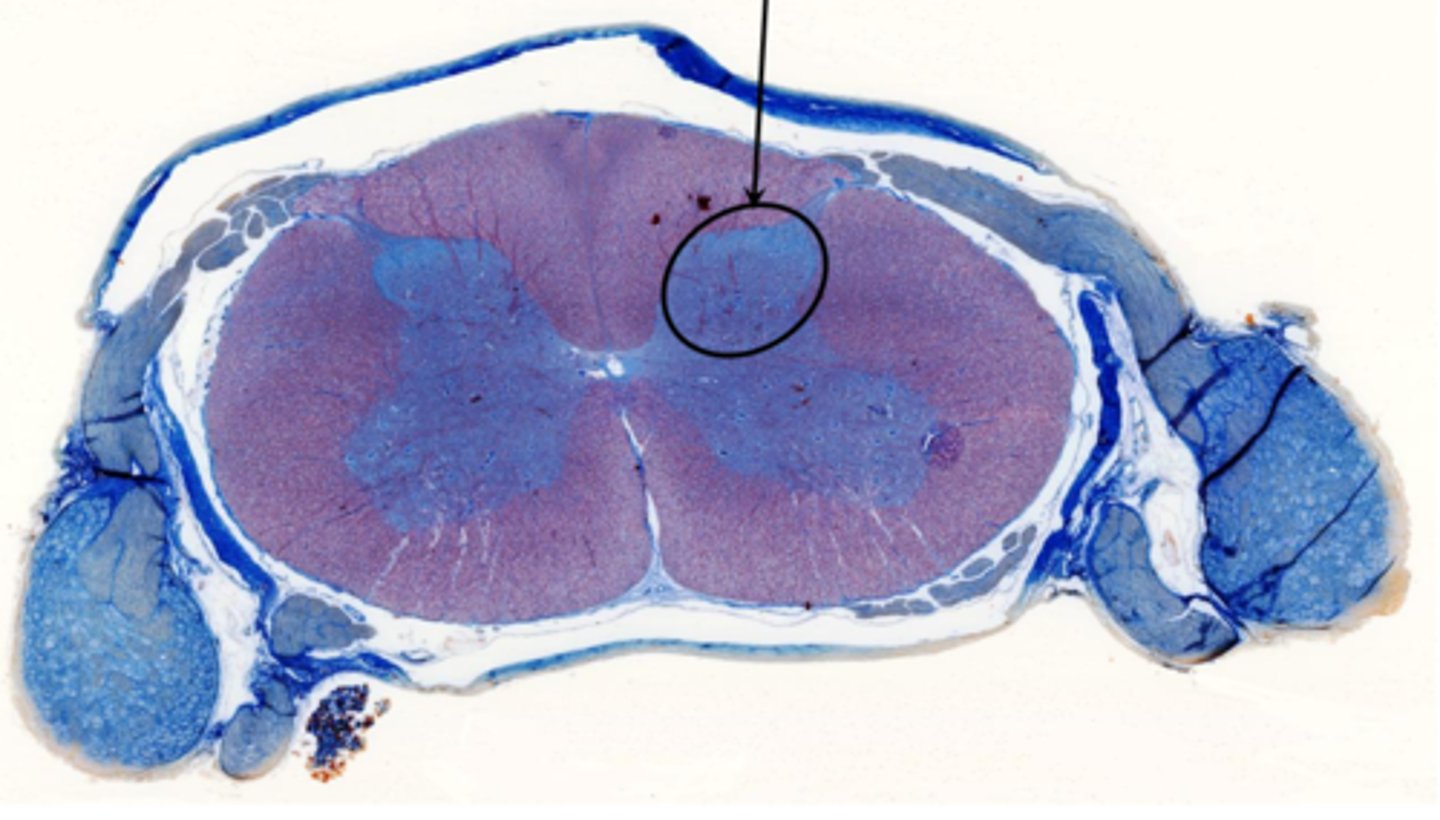

Identify the part of the spinal cord

dorsal funiculi

lateral funiculi

ventral funiculi

dorsal horn

ventral horn

dorsal root of spinal nerve

ventral root of spinal nerve

What is the midline structure that separates the dorsal left and right halves of the white matter

dorsal median septum

What is the midline structure that separates the ventral left and right halves of the white matter

ventral median sulcus

Identify the section of the spinal cord that contains nuclei

gray matter

Identify the section of the spinal cord that contains nerve tracts

white matter

central canal

Identify the cluster of neurons circled

nucleus of the deep cerebellum